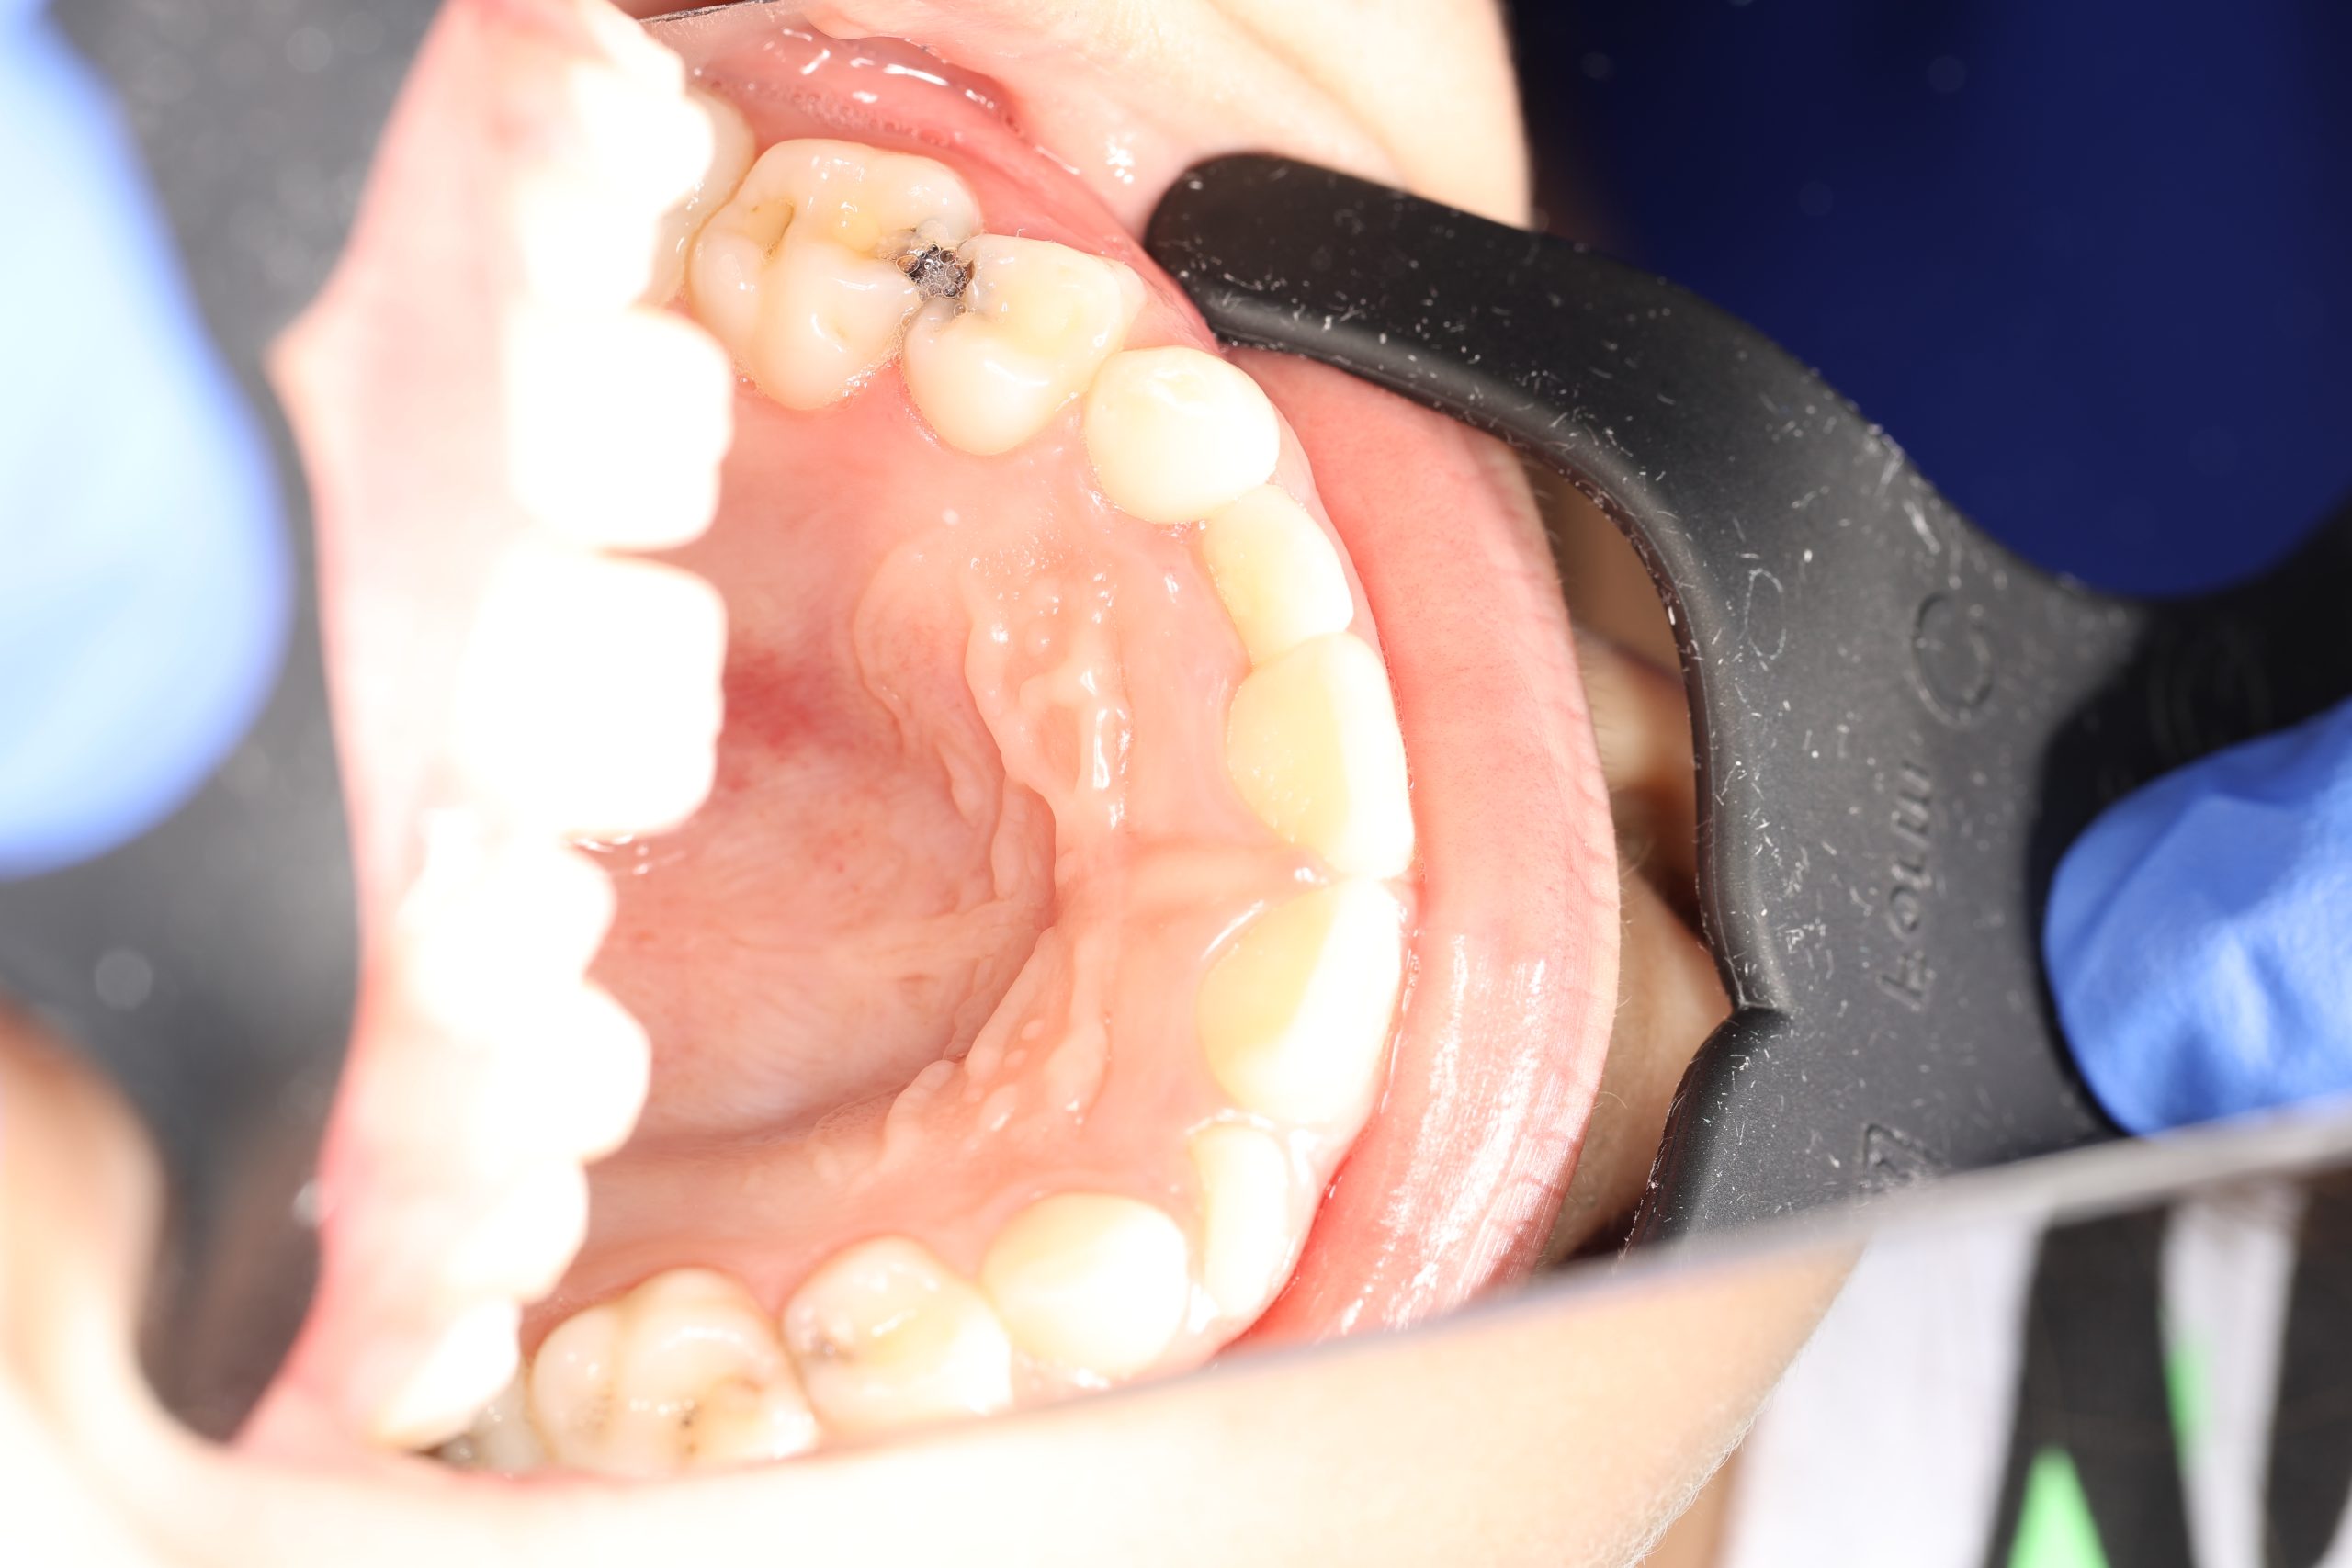

Stainless Steel Crowns (SSC)

The most popular type for back baby teeth. Durable, cost-effective, and fast to place, they provide excellent protection against further decay.

- Examination and Diagnosis: We assess the tooth to confirm that a crown is needed.